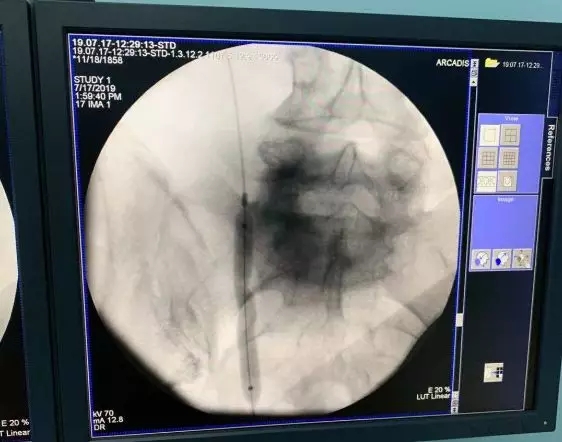

为保护患者右肾功能以及治愈右侧输尿管狭窄,经科室讨论后,决定Ⅰ期先行右输尿管镜检+右侧输尿管狭窄球囊扩张术;Ⅱ期行右侧输尿管狭窄ALLIUM支架植入术。Ⅰ期术中发现右侧输尿管中段迂曲并瘢痕狭窄形成,使用球囊扩张器将狭窄部位扩张。

术中检查发现明显“蜂腰征”,提示右侧输尿管中段狭窄

术中使用输尿管球囊扩张器将狭窄部位扩开